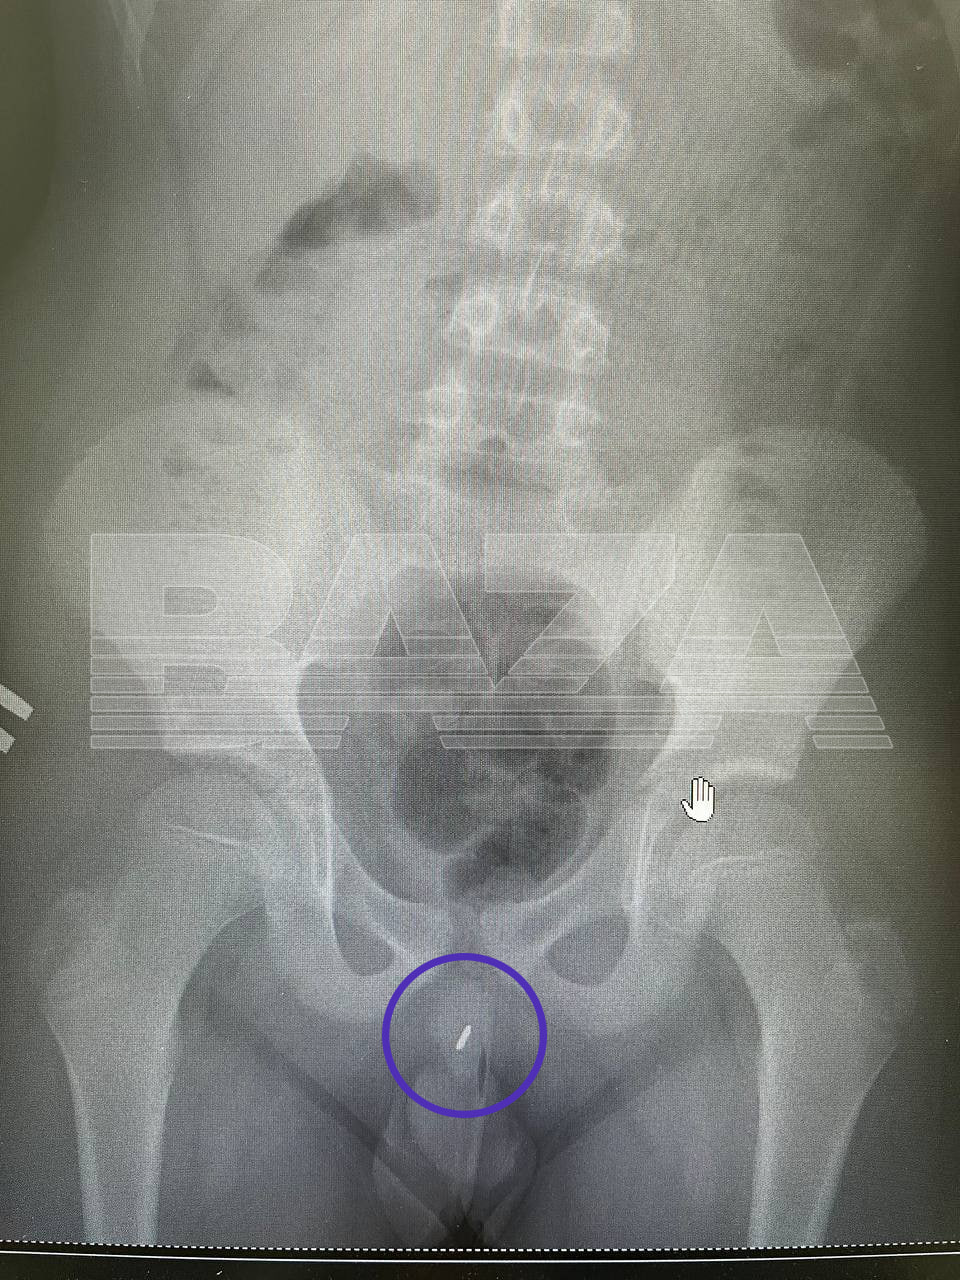

Подмосковные врачи достали 7-сантиметровую иглу из мочеиспускательного канала 11-летнего мальчика. Очень любопытного мальчика.

Пацан пришёл с родителями в Московский областной центр охраны материнства и детства с жалобами на боль при мочеиспускании. Врачи сделали рентген и сильно удивились — в мочеиспускательном канале мальчика была большая игла. На вопрос, как она туда попала, парень сказал, что он просто игрался.

Достать 7-сантиметровую иглу смогли без операции и разрезов, методом цистоскопии, при которой используют специальные миниатюрные щипцы и мини-камеру. Парня уже выписали, а врачи отмечают, что дети пубертатного возраста на фоне гормональной перестройки организма могут проявлять повышенный интерес к изменениям своего тела.